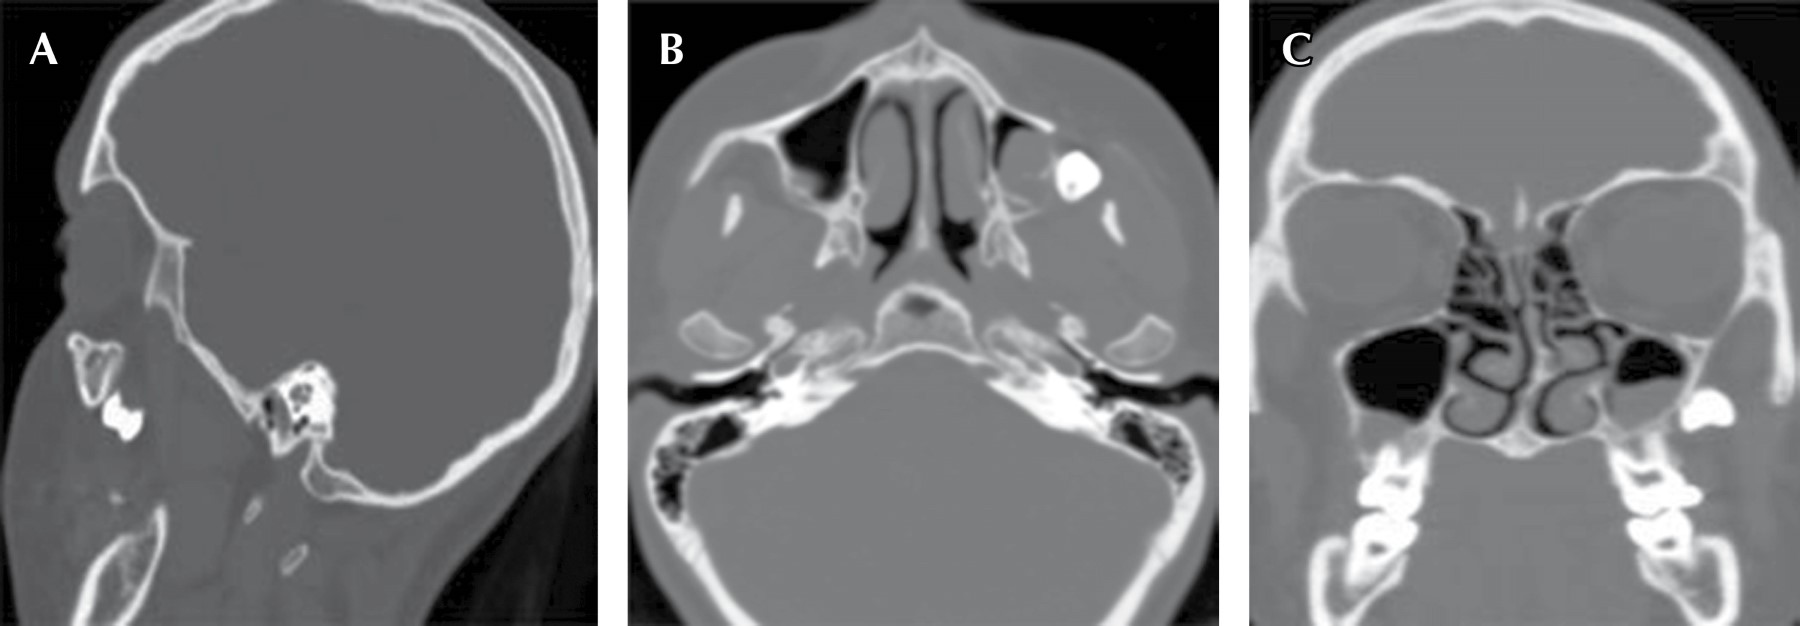

La recuperación de la unidad dentaria desplazada puede ser mediante un abordaje intraoral como fue expresado anteriormente, o extraoral como lo presenta Nadeem A y su equipo en el estudio denominado: A rare case of mandibular third molar displaced into submandibular space: A complication of mandibular third molar extraction10 en el cual mencionan el caso de un paciente masculino de 44 años de edad, en donde en una cirugía anterior ocurrió el desplazamiento del tercer molar inferior izquierdo, al realizar los estudios radiográficos y una tomografía computarizada, se dio a conocer la ubicación exacta del tercer molar el cual se encontró en la zona submandibular (Figuras 5 y 6); el abordaje fue realizado mediante un colgajo lingual, bucal y una incisión en la zona submandibular, ya que la unidad dentaria se encontraba muy profunda, sin embargo, con buena iluminación lograron encontrar la unidad dentaria y con una cureta se pudo traccionar el molar hacia el exterior (Figura 7). A diferencia de los casos de desplazamiento de terceros molares, en los cuales el único abordaje posible es de manera extrabucal, como expresan Shruthi TM y colegas en el estudio tipo reporte de caso: Removal of Displaced Maxillary Third Molar Using Modified Gillie's Temporal Approach11 donde presentan a un paciente femenino de 26 años de edad cuyo tercer molar superior derecho fue desplazado durante la osteotomía del hueso maxilar Le Fort 1, para el reposicionamiento del hueso maxilar por aumento de la dimensión vertical; el tercer molar fue desplazado hacia los tejidos más profundos y no se podía palpar, en la misma cirugía se intentó recuperar el tercer molar a través de la incisión intraoral que ya se había realizado para la osteotomía, pero no se tuvo éxito. Se indicó la realización de una tomografía computarizada lo cual reveló que el tercer molar fue desplazado hacia la fosa infratemporal (Figura 8). Por su ubicación se decidió realizar un abordaje extraoral mediante un "abordaje temporal de Gillies modificado", el tercer molar fue encontrado y recuperado con éxito. De la misma manera, Oliveira MMM y colaboradores en el estudio Third Molar Displacement into Submandibular Space,12 reportan el caso de un paciente masculino de 21 años quien durante la cirugía para la extracción del tercer molar inferior izquierdo experimentó el desplazamiento de un fragmento de la unidad dentaria. Durante la cirugía el operador intentó recuperar el fragmento pero no tuvo éxito. Se indicó la realización de una tomografía computarizada Cone Beam, para la revisión y ubicación del mismo, el cual se encontró en el espacio submandibular (Figura 9). Para la recuperación del fragmento se decidió realizar un acceso extraoral en la región submandibular bajo anestesia general, la unidad dentaria se pudo recuperar con éxito (Figura 10).

Figura 5

Figura 6

Figura 7

Figura 8